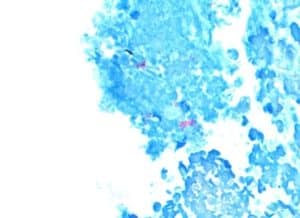

Figure 5: AFB stain shows focal area with aggregated pink rods showing AFB (10x, scale bar 500 lm)

Figure 6: GMS stain for fungi shows a single small aggregate of rare fungal hyphae (20x, scale bar 500 lm)